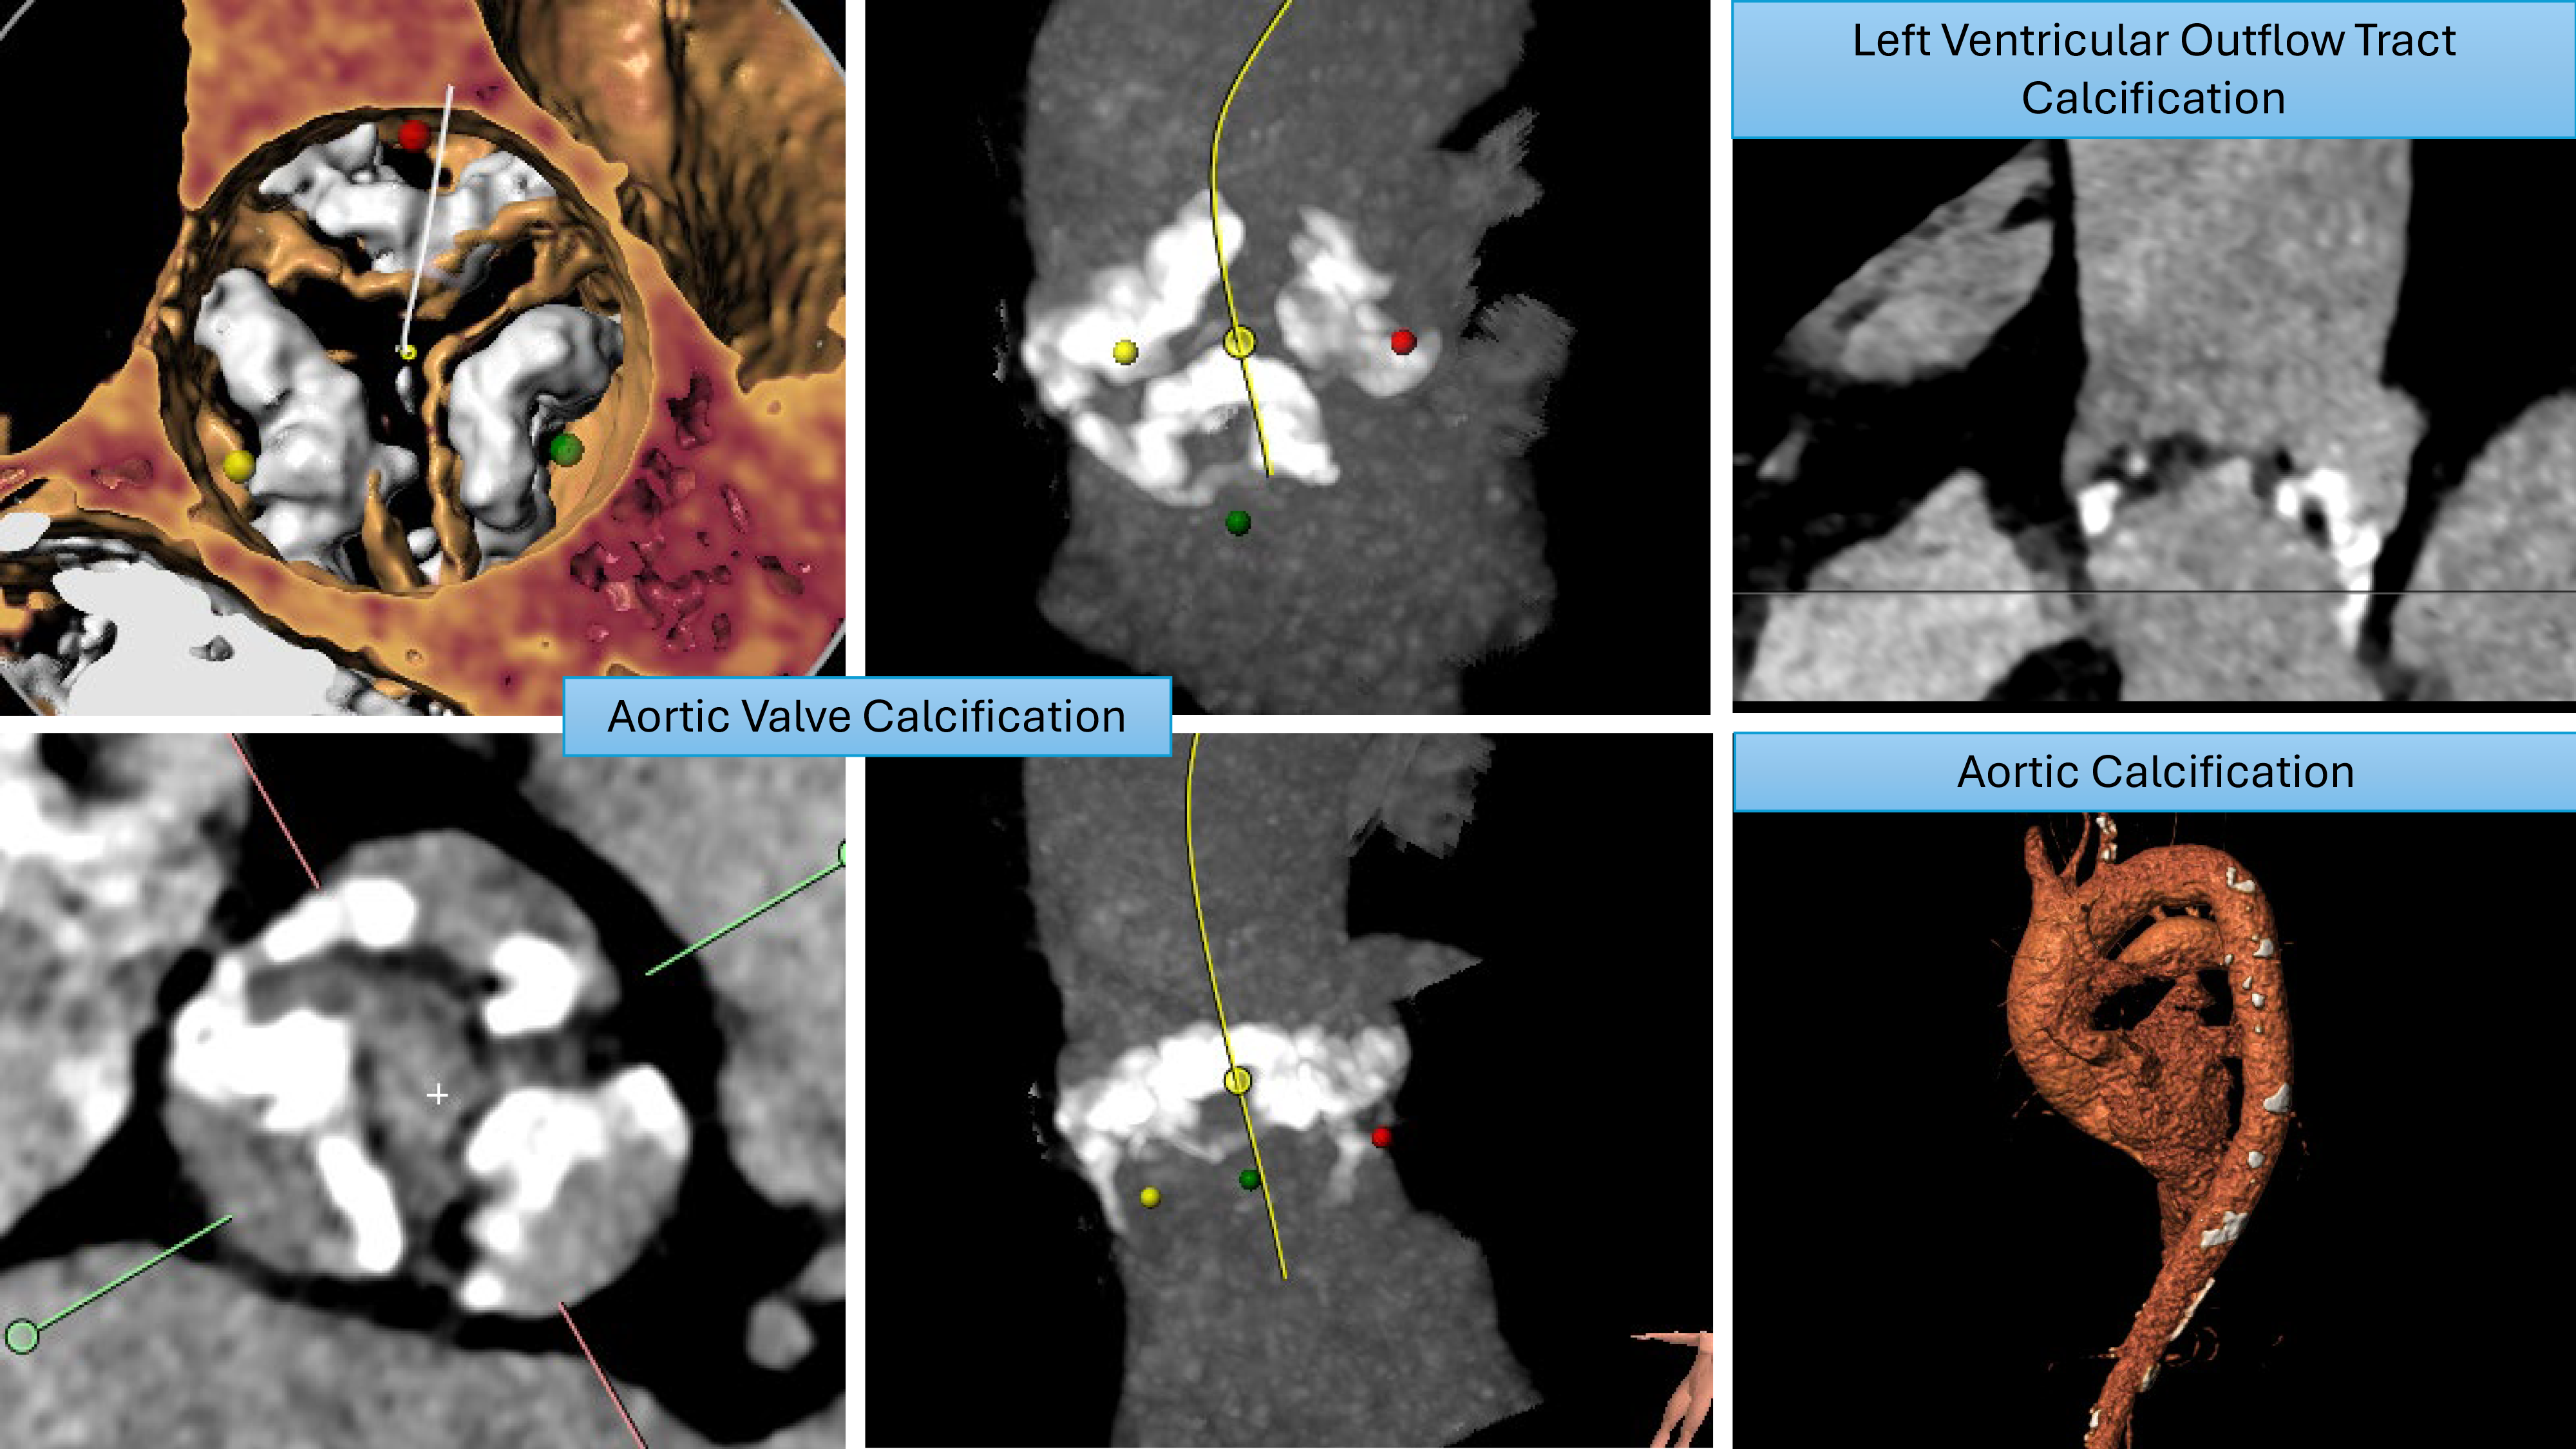

Increased aortic valve calcification increases the risk of acute stroke peri-procedurally due to the increased debris generated during the procedure. Pollari et al. [47], in a retrospective study analyzing computed tomography (CT) scans pre-TAVI procedure, reported a significantly increased risk of stroke associated with left ventricular outflow tract calcification. This was further evidenced by Maier et al. [48] in a retrospective study investigating risk factors for stroke post-TAVI, who reported a higher calcium volume, specifically in the left ventricular outflow tract (LVOT) and right coronary cusp (RCC), which was associated with higher stroke rates. Examples of significant aortic root calcification, which may increase stroke risk during TAVI, are illustrated in Fig. 2.

Fig. 2. Patterns of calcification that increase stroke risk.